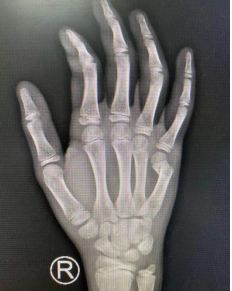

徐州丰县的13岁男生昌昌(化名)周末放假在家,与妈妈因一件小事意见不合,一气之下攥紧拳头,转过身狠狠地撞击墙面。随后他感觉右手疼痛、肿胀,活动受限。妈妈赶紧带着孩子到当地医院就诊,检查显示患儿右手第五掌骨骨折,医生为他进行了夹板外固定治疗。为进一步治疗,妈妈又带着孩子来到我院,手外科一病区的孙传伟医生接诊。

术前